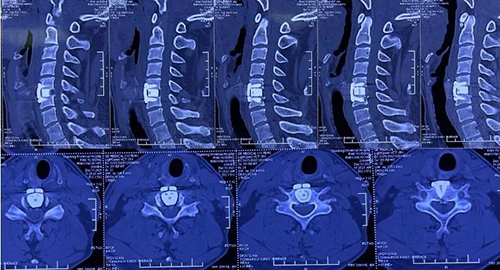

颈椎病例为49岁男性患者,主诉“双下肢走路不稳2月余,加重1月”。查体发现患者颈椎曲度变直并局部后凸。颈椎MRI显示C3/4、C5/6、C6/7椎间盘突出并椎管狭窄,C5/6水平脊髓变性。诊断为脊髓型颈椎病,颈椎间盘突出症。

该患者颈椎曲度变直并局部存在后凸畸形,通常这种颈椎融合手术应用不同规格的PEEK材料椎间融合器,术中椎间压配不良,术后植骨融合效果不确切。丰荣杰主任医师详细制定治疗策略,决定为患者进行显微镜辅助下颈椎前路减压植骨融合内固定术。通过使用3D打印钛合金椎间融合器,使融合器与椎板紧密解剖型贴附,增加了骨接触面积,能够获得即刻稳定。这种多微孔的结构可使自体骨直接长入,避免大量异体骨的使用,同时可有效纠正后凸畸形,从而实现在患者正常颈椎生理曲度下的完美融合。

术前CT

术后CT